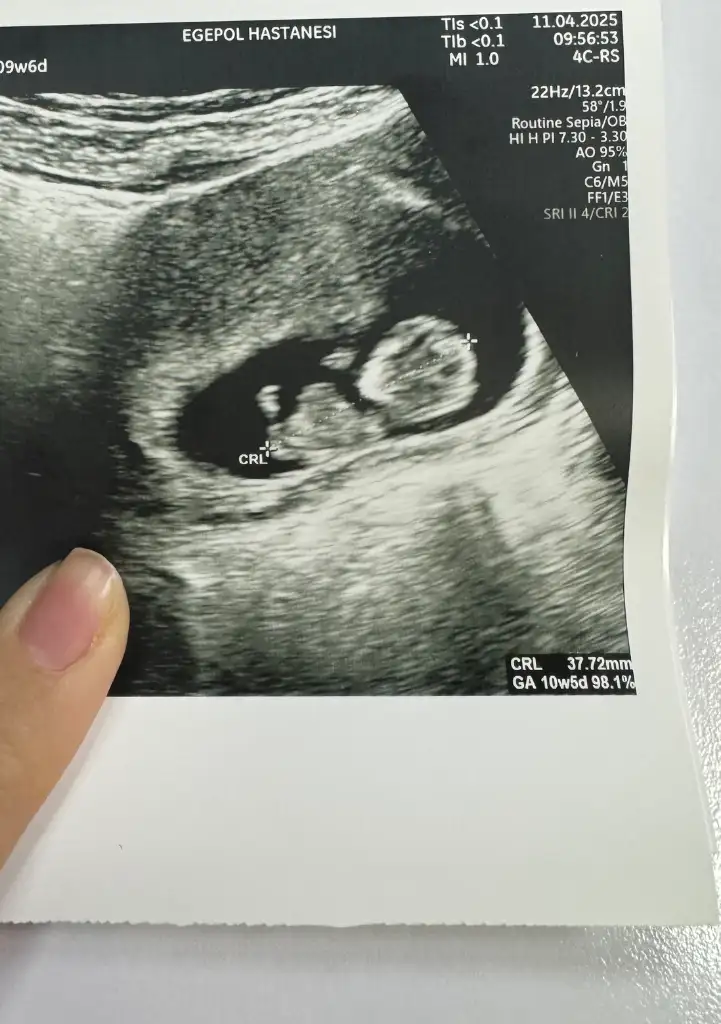

Ooy minik kuzu geldiAhhh kızlarrr aşkımı gördüm miniğimi gördümmm büyümüş serpilmiş hareket ediyordu

Ay harika bi fotograf olmuş. Cinsiyet ile ilgili bir sey söyledi mi dr?Ahhh kızlarrr aşkımı gördüm miniğimi gördümmm büyümüş serpilmiş hareket ediyordu

Canım hiçç sormak aklıma gelmedi cünkü onun hareketlerini görünce çok ağladım. Sırtüstü geriniyor uzanıyor kıpırdıyor ahh allahım hepimizi böyle müjdelerle sevindirsin..Ay harika bi fotograf olmuş. Cinsiyet ile ilgili bir sey söyledi mi dr?

Ahhhhh bi güzel büyümüş ki teyzesiii. Bugün 9+6 ama ısgde 10+5 cıktı doktor uzun olacak dediOoy minik kuzu geldimasallah cilekcim sabah sabah gozumuz gonlumuz acildi

yaaa eridim şuandaaa nasıl da büyümüş annesii sata göre önde çıkmış sanki ne diyosunAhhh kızlarrr aşkımı gördüm miniğimi gördümmm büyümüş serpilmiş hareket ediyordu

Yaaaa Maşallah ona. Bakar bakmaz içime bir prenses olduğu doğdu. Hadi hayırlısı sağlıkla gelişsin minik kuşAhhh kızlarrr aşkımı gördüm miniğimi gördümmm büyümüş serpilmiş hareket ediyordu

Evet teyzesi yaaa o kadar narin o kadar tatlıydı kiiiyaaa eridim şuandaaa nasıl da büyümüş annesii sata göre önde çıkmış sanki ne diyosunyaa bişey diyeyim mi içime kız doğdu şuanda senin için neden bilmiyorum usg de çok narin çıkmış resmen bir kız bebek gibi

Ayy yesinler onu ya maşallah maşallah güzel bakmışsın annesi hasretini gidermişsindir dimiEvet teyzesi yaaa o kadar narin o kadar tatlıydı kiiiUsgde 1 hafta kadar önde gidiyor, doktor uzun boylu olacak dedi ne yedin kız büyütmüşün bu bıdığı böyle diyor